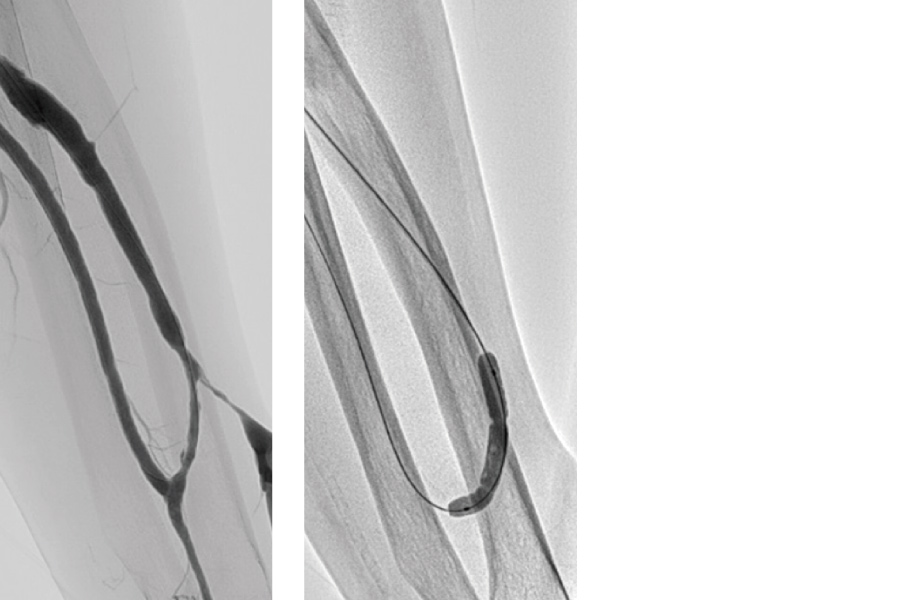

静脈の血栓

腸骨静脈に血栓閉塞が起きて、左下腿のむくみ、うっ滞がでた患者様。治療後、速やかに改善しました。